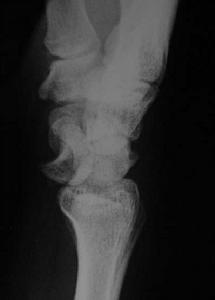

月骨脫位--CT月骨周圍脫位者,月骨留在原位,其他腕骨向背側移位,並向橈側變位形成畸形。X線正位片顯示,脫位的月骨呈三角形(正常月骨應為四方形)。且投影與頭狀骨下端重疊。側位像顯示,月骨脫向掌側,半月形凹面也轉向掌側。

月骨脫位--檢查(1)X線正位片:可見腕骨排列紊亂,頭狀骨與月骨影重疊,舟月間隙增大,舟骨長軸變短,呈皮質環征或舟骨鏇轉,月骨脫位失去四邊形結構,呈三角形影。

(2)X線側位片:出現月骨周圍背側脫位,第3掌骨、頭狀骨與月骨、橈骨失去正常共軸線關係,第3掌骨及頭狀骨的軸線位於月骨及橈骨軸線背側,在此基礎上當月骨向掌側傾斜時,提示為動態性月骨周圍背側脫位,月骨掌側脫位時可見第3掌骨、頭狀骨、橈骨共軸承關係不變,而月骨位於以上諸骨軸線掌側。

月骨脫位X線正位片可見月骨輪廓,由梯形變為三角形。周圍關節間隙不平行或寬窄不等,側位見月骨掌側脫位輕者,月骨仍位於橈骨遠端凹面內,掌屈過度,橈月關節背側間隙變寬,頭狀骨與月骨背側面相對重者,月骨掌屈大於90°進入腕管內與橈骨遠端、頭狀骨完全分離。月骨周圍脫位與月骨脫位X線片影像雖然顯著,但漏診率至今仍居高不下。恐怕與X線側位片骨影相互重疊,單一腕骨輪廓難於分辨有關。診斷困難者可做CT檢查。

根據X線片檢查不僅可以明確診斷,尚可對脫位類型進行分類。正常時腕關節正位片上月骨呈四方形,位於橈骨與頭狀骨之間,在側位片上頭骨、月骨、橈骨三者呈直線關係排列,上述關係的異常很易在X線上發覺,因此診斷並不困難。